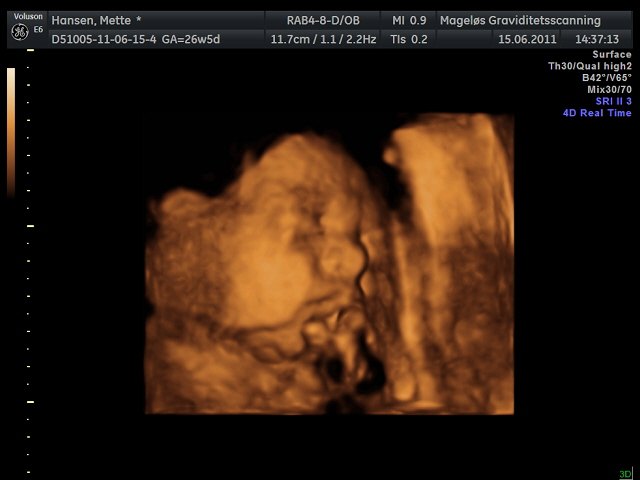

Mettefpigen

Hvor er de flotte de billeder i har lagt ind

Her er det min lille dreng  Han ville selvfølgelig ikk vise hele sit ansigt så har kun fået "noget" af det

Hihi men fik faktisk også et billede af hans dutti, så nu er vi 100% sikker på at det er en dreng  haha.. Så har vi det først billede til hans konfirmation

Vedhæftede fotos (klik for at se i fuld størrelse)